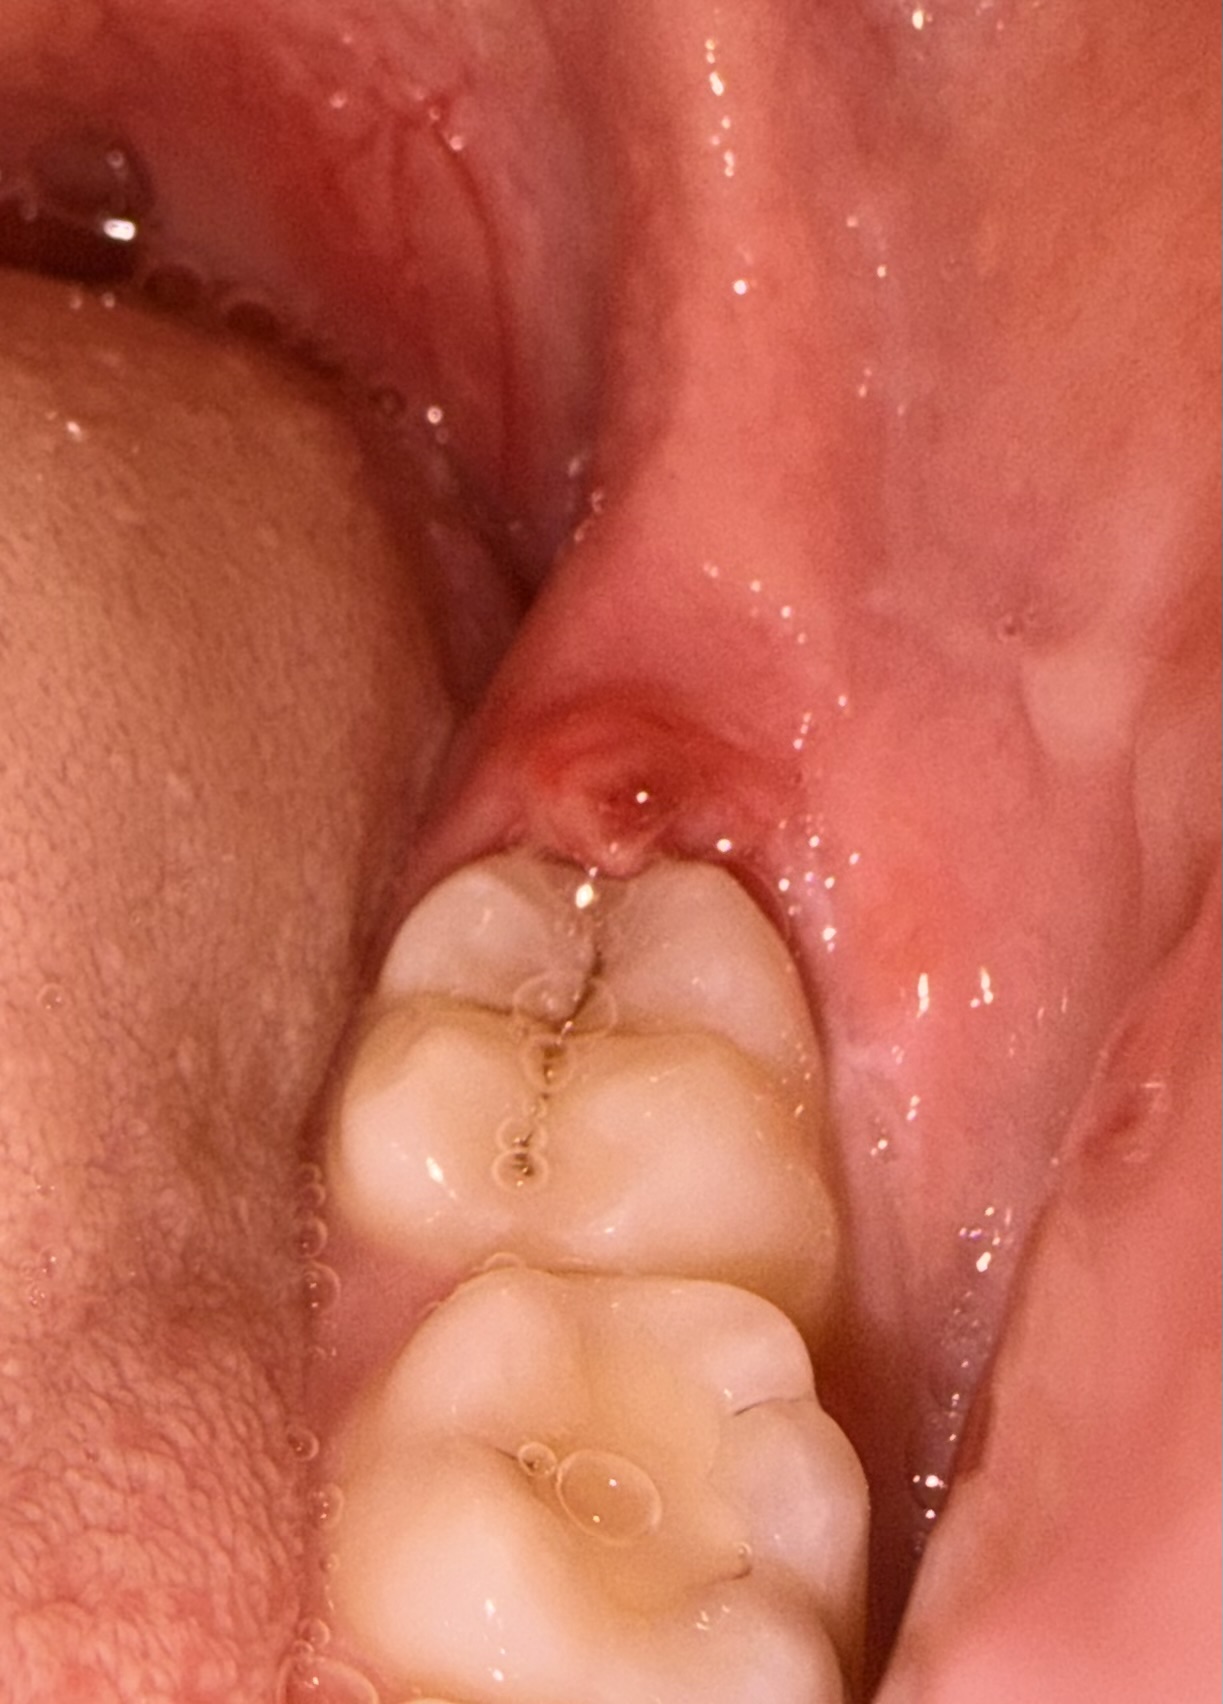

Het tandvlees bij mijn verstandskies komt los en begint steeds te ontsteken. Ik moet volgende maand mijn verstandskiezen laten en trekken en dan moet het verholpen zijn zegt mijn tandarts. Normaal word het flapje rood en opgezwollen en na 3 a 4 dagen is het weer hersteld als ik perio aid gebruik. Nu heb ik er al een week last van en begint het flapje er ook raar uit te zien. Nu zit er iets wits omheen en gister was het knalrood. Ik weet niet zo goed wat ik ermee aan moet, het doet namelijk ook best veel pijn. Mijn eigen tandarts is op vakantie en de vervangende zit helemaal vol, vandaar dat ik de vraag hier maar stel. (De foto’s staan als het goed is met de eerste maandag tot vandaag de laatste foto)